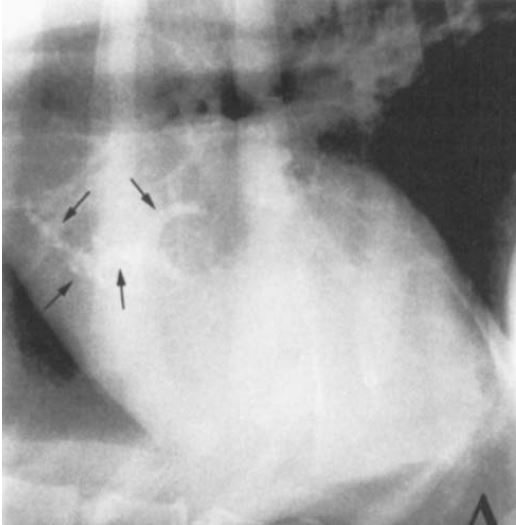

Douglass et al: Radiographic features of aortic bulb mineralization in dogs, what were the two types of mineralization patterns?

1. Curvillnear single strand

2. Multiple mineralizations (pictured)